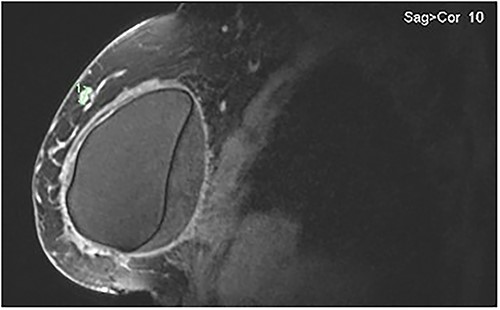

Bilateral breast MRI demonstrated intact implants, the known right-sided IDC and a right-sided septated collection of peri-implant fluid (Fig. 4). Aspiration of 20 mls of turbid fluid did not show evidence of an atypical or aberrant lymphoid population by cytology or flow cytometry.

MRI of the right breast demonstrating peri-implant effusion and the confirmed IDC in the upper outer quadrant at the 9 o’clock position.